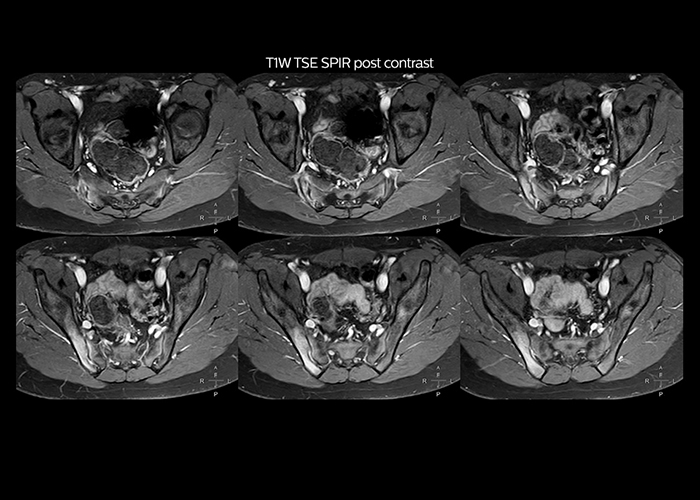

“On average, we scan about 80 patients per day, but on some days we scan well over 100 patients. The scanner is in use 7 days per week, operated 20 hours per day on week days and 8 hours per day in the weekend,” Mr. Tuna says. “To avoid coil changes we plan examinations of similar anatomies back to back, such as head and spine. Multiva helps us here a lot because coils don’t need to be changed frequently. Moreover, thanks to parallel imaging technology and 16-channel HeadSpineTorso and 8-channel MSK coils we are able to achieve excellent image quality. In this way Multiva helped us to increase both image quality and productivity.” “Neurological cases, such as brain and spine imaging, represent the largest share in our MR scanning, followed by musculoskeletal cases. In general, we use simple and basic imaging protocols. But occasionally, we use advanced techniques for problematic cases if necessary.

“Since we have Multiva, we have improved our workflow, because it has been so easy for our operators to learn and use Multiva. Our operators notice that the coils are lightweight and coils don’t need to be changed frequently. The user interface is easy to use. Features like this help us to scan a high number of patients. For instance, the musculoskeletal coils can be used interchangeably, and due to the user-friendly interface, the number of mistakes such as, for example, correct coil element selection has decreased significantly, because the system does it automatically by itself.” “Most important, Multiva satisfies our clinical imaging needs very well,” says Mr. Tuna. “Many features of Multiva have become similar to the Ingenia system. Even in more complex imaging such as abdominal and cardiac, the image quality and performance of Multiva is better than we expected. General surgeons and physicians from our hospital’s internal medicine department prefer to refer to us because of this.”

“Overall, Multiva provides what we need in term of patient needs and even potential needs,” says Mr. Tuna. “It allows us to scan a high patient volume and image a large variety of anatomies and conditions.” “Our goal is to achieve uncompromising quality based on universal standards, while solving clinically complex cases. Our Multiva scanner allows high productivity with fast imaging time, and allows us to make confident diagnoses in a broad range of cases.” “It’s an excellent multi-purpose scanner that satisfies all our MR imaging requirements in the hospital,” he concludes.